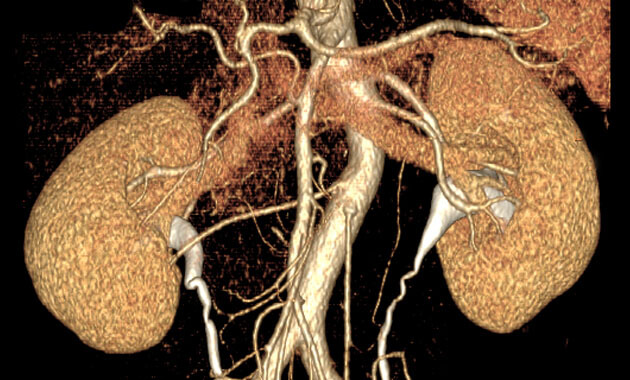

The Abdominal Imaging Division of the UC San Francisco Department of Radiology and Biomedical Imaging is made up of internationally recognized abdominal imaging experts who diagnose and treat disorders of the liver, pancreas, colon, uterus, ovaries, prostate, and bladder. The Abdominal Imaging Division is focused on serving patients, conducting research, and training the next generation of radiologists.

- Kidney cancer (including renal cancer)

Kidney Cancer: Why Tumor Ablation May Be a Good Treatment Choice

Kidney Cancer: Why Early Treatment is Critical